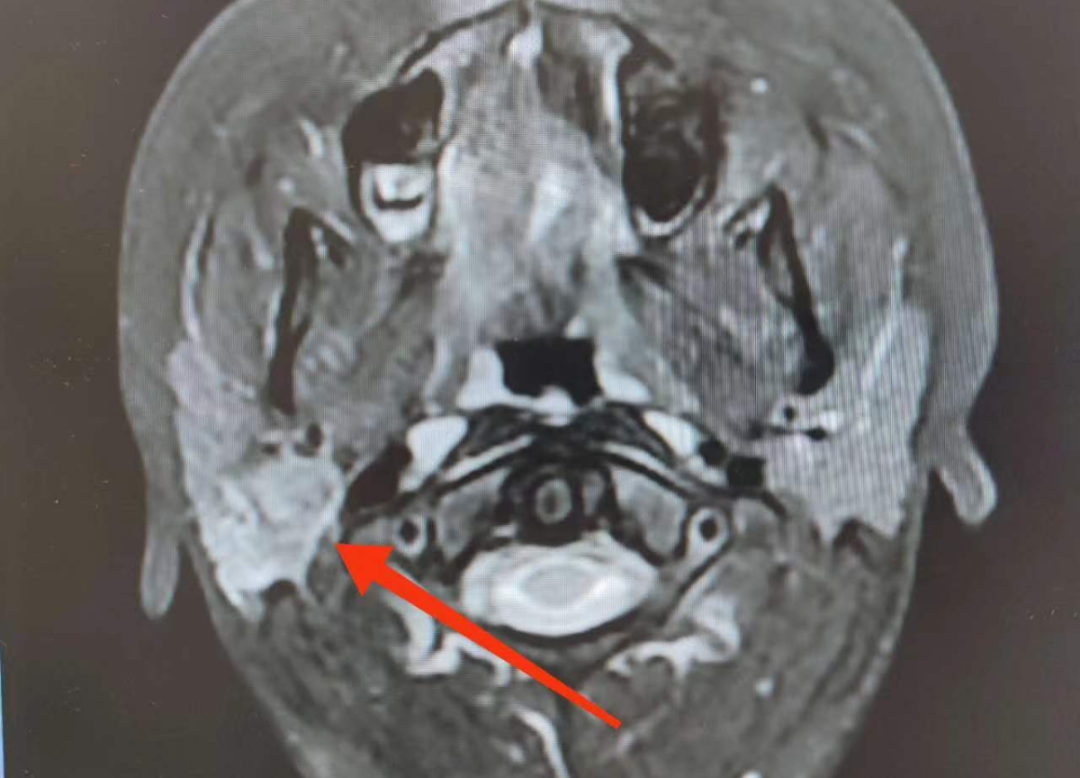

于是家長帶她來到青島市婦女兒童醫(yī)院口腔頜面外科門診就診,MR檢查提示:右側(cè)腮腺內(nèi)見斑片狀、囊狀病變,約2.6*1.6cm大小。醫(yī)生考慮“腮腺區(qū)腫物”,建議玲玲入院手術(shù)治療。